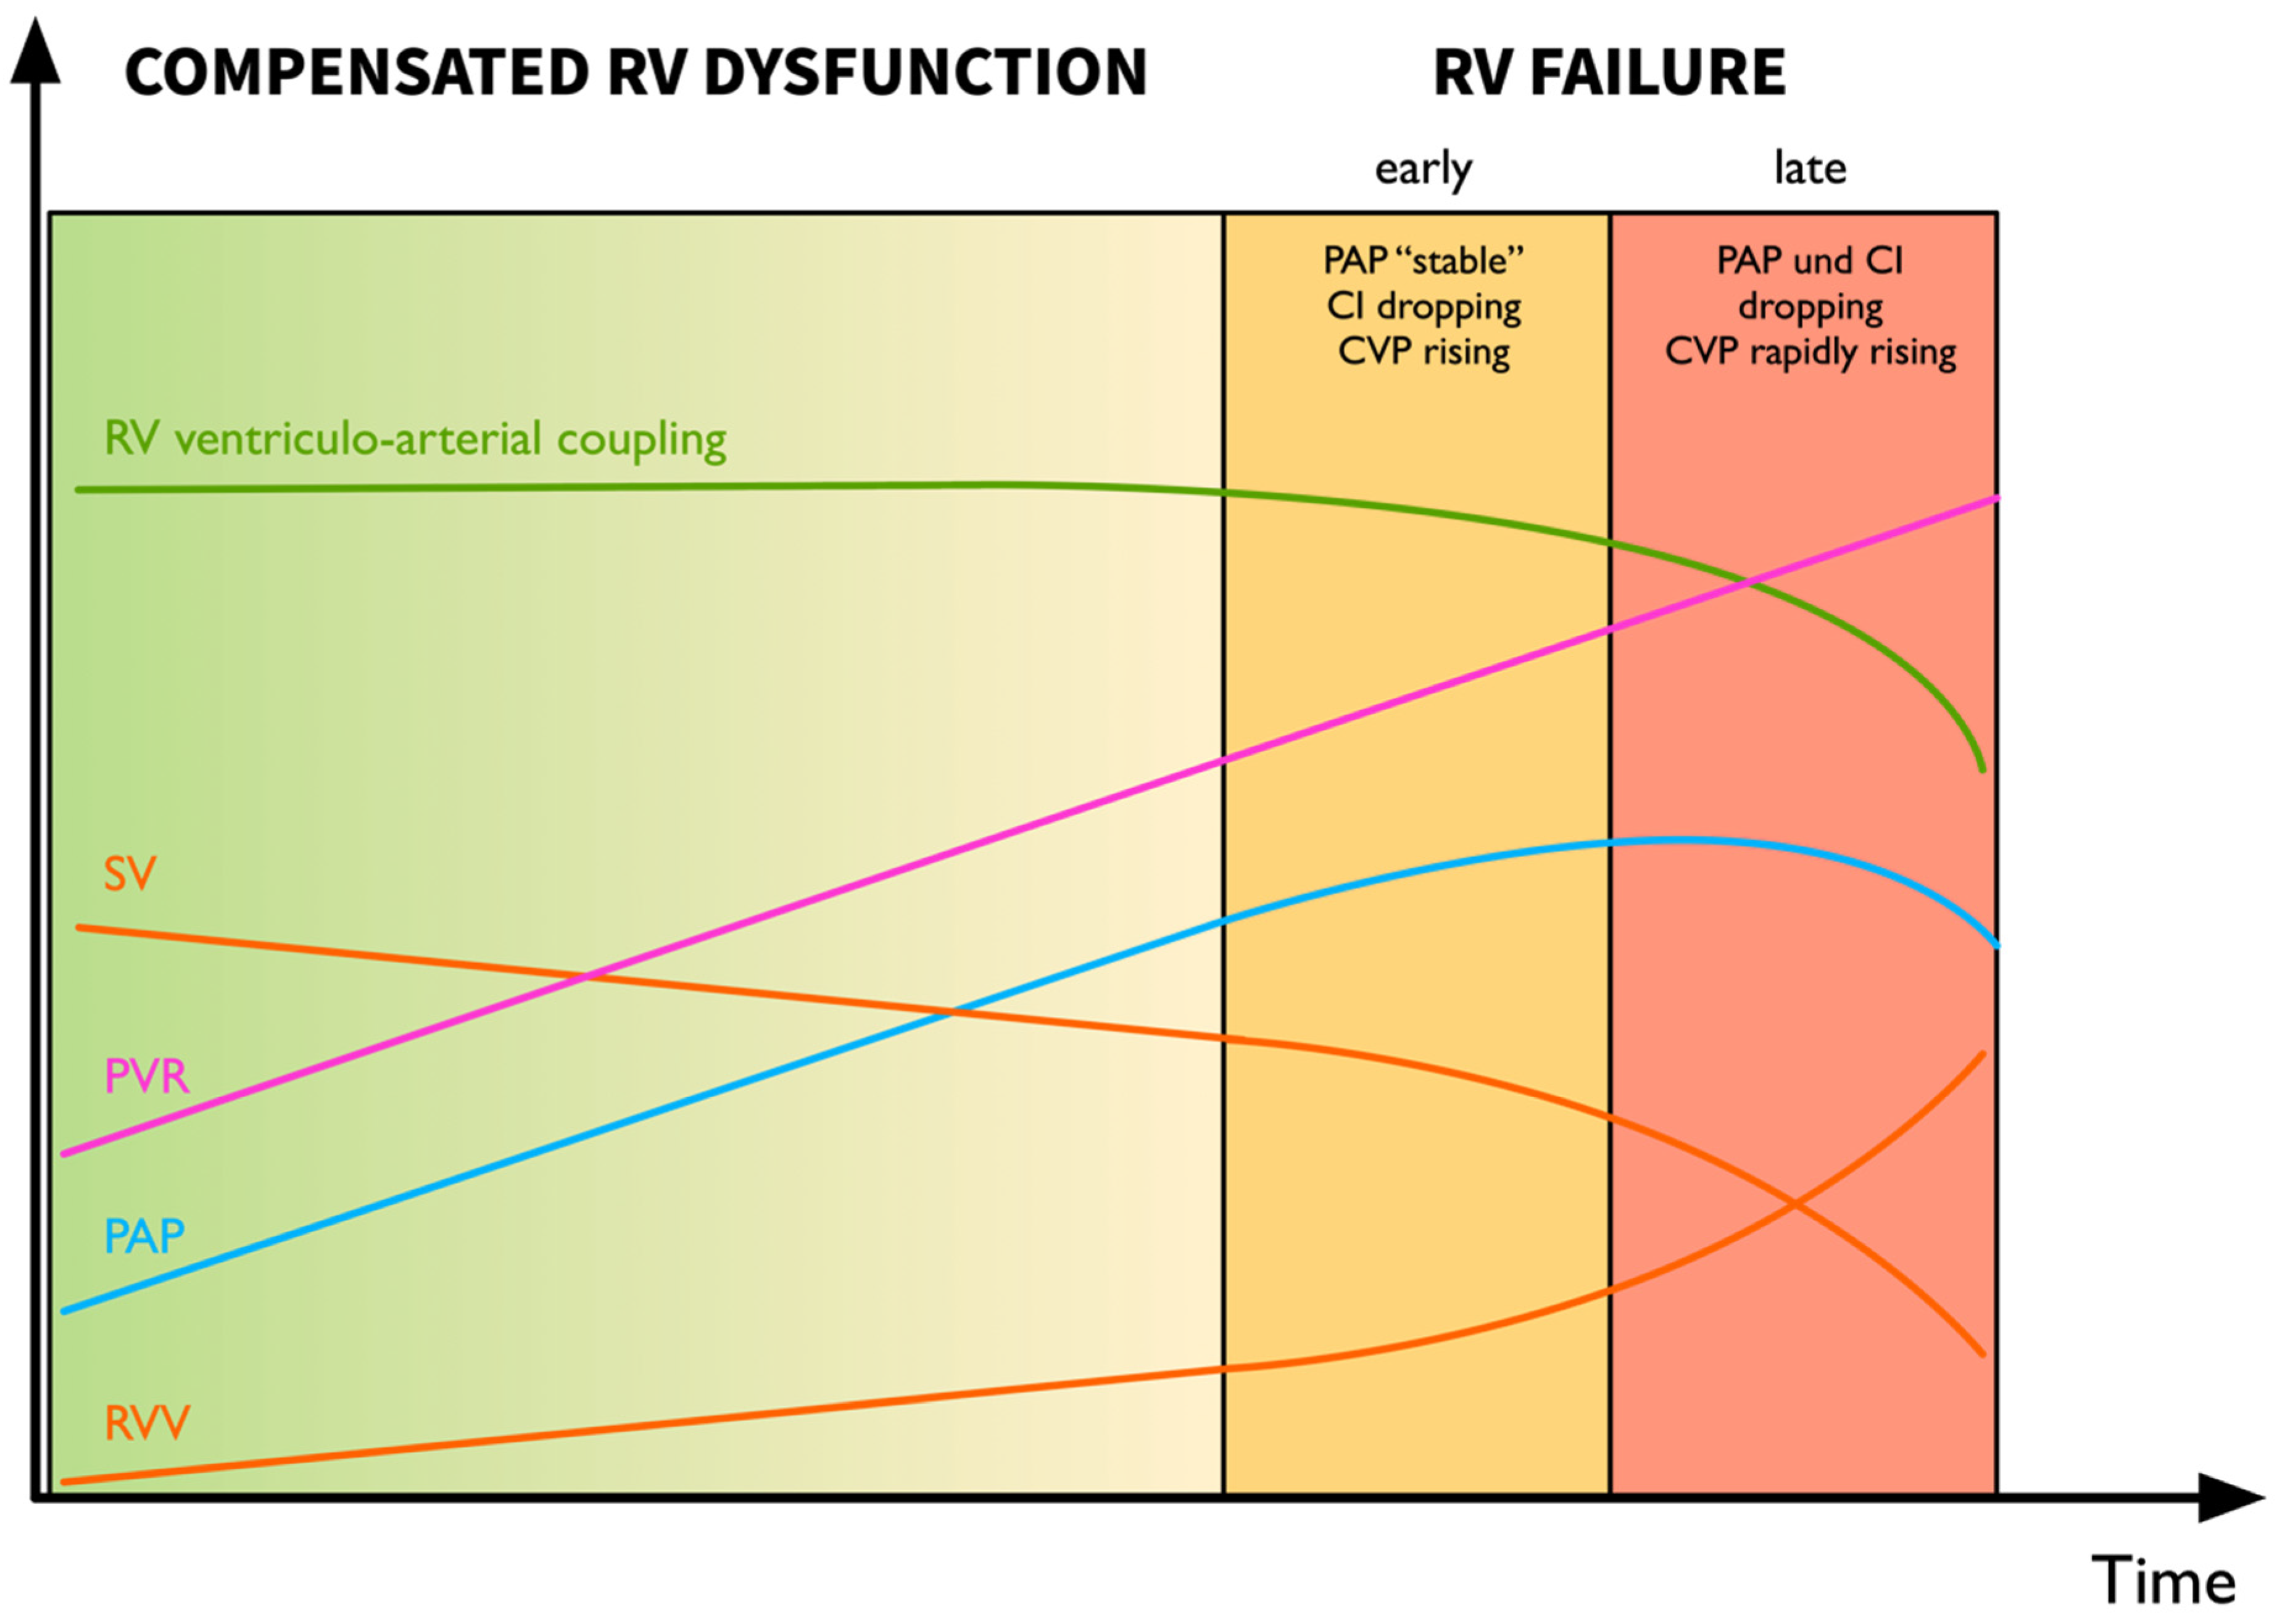

4.2.4. Recognition of the Decompensating Right Ventricle—Pressure Does Not Equal Flow